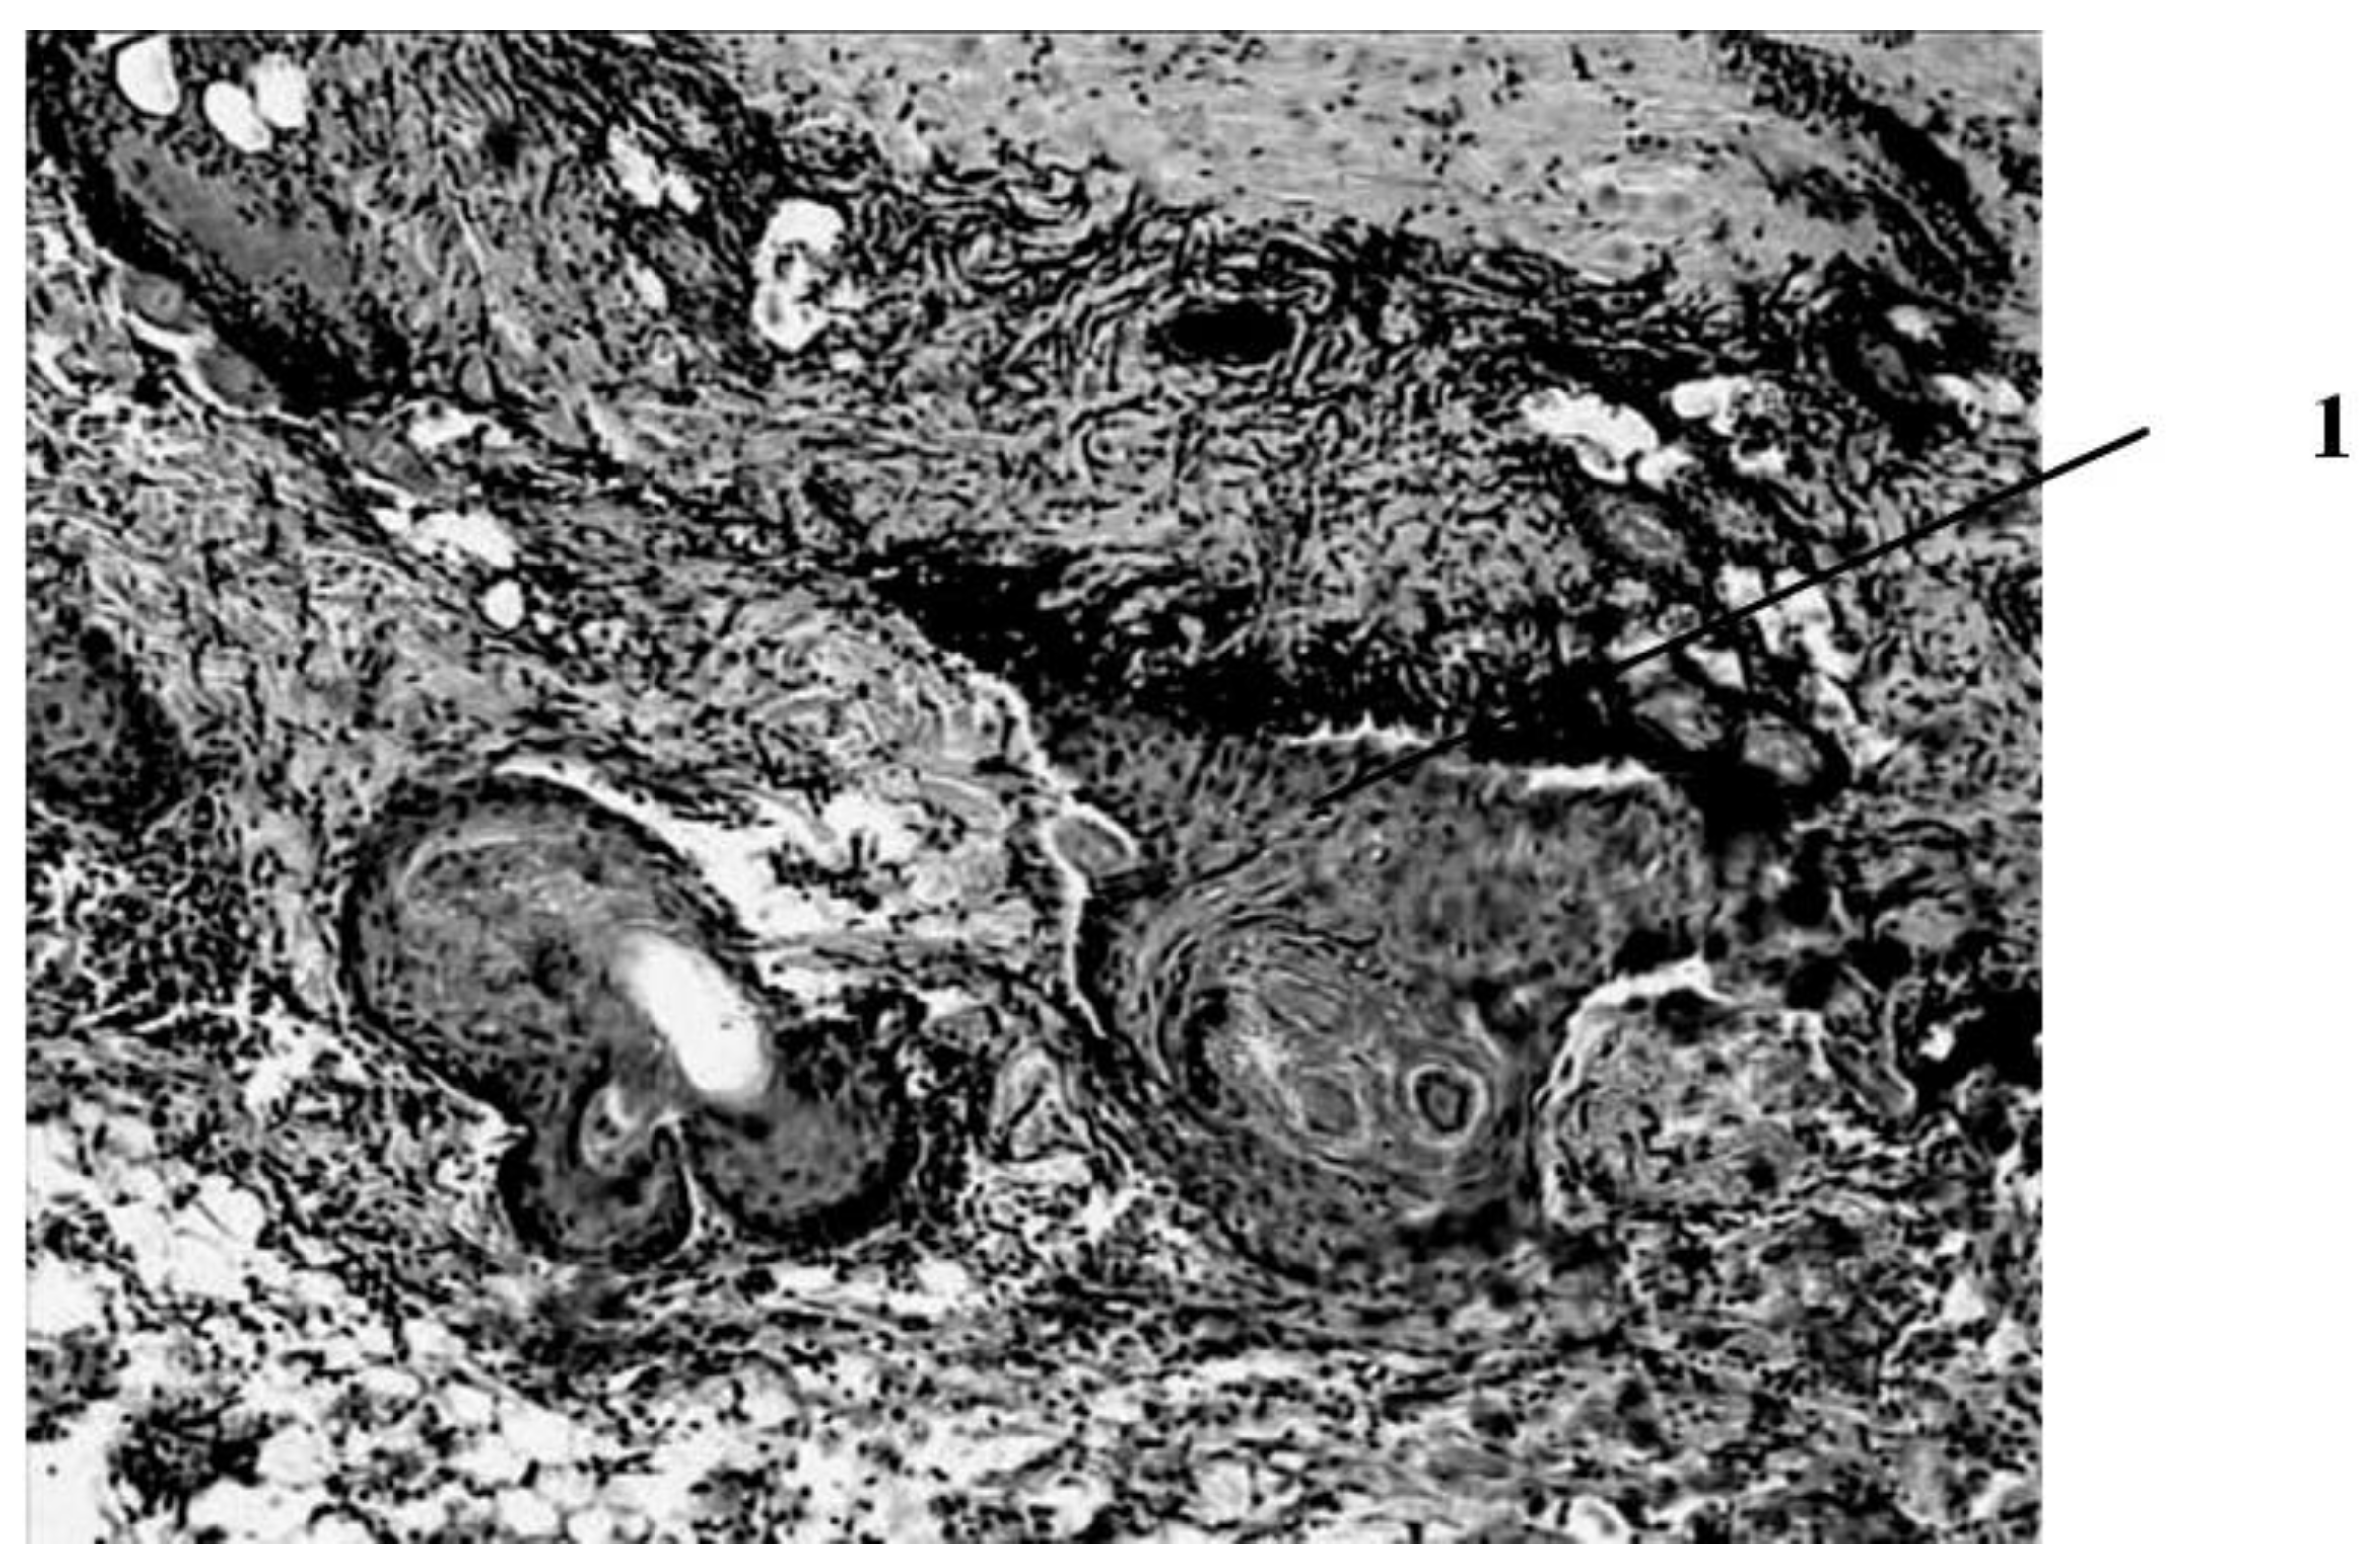

Seven days after the burn, in animals that had a wound punctured daily with a gas mixture with ozone, the scab partially separates from the wound surface as a result of penetration of a growing layer of epidermis under it (Figure 4).

This is the marginal epithelization of the wound, in which the proliferating epithelium of the deep sections of the hair follicles preserved in the lower layers of the dermis also takes part. The separation of the scab follows the line of a clearly expressed solid leukocyte demarcation shaft. In the center of the wound bottom, necrosis of the skin’s own muscle is noted for its entire thickness and infiltration of necrotized muscle fibers by leukocytes. In the muscle layer located to the periphery of its necrosis zone, there are phenomena of muscle fiber regeneration in the form of proliferation of myocyte nuclei and neoplasm of thin muscle fibers with basophilic cytoplasm. Under the layer of the skin’s own muscle, a hemorrhage site containing nonhemolysed erythrocytes is visible, and along its periphery there is fibroblast proliferation and manifestations of neoangiogenesis. Individual newly formed capillary-type vessels grow into the hemorrhage zone. There is also a pronounced proliferation of epithelium in the hair follicles located in the deep layers of the dermis. Thus, seven days after the burn, under conditions of pricking wounds with an ozone-containing gas mixture, more pronounced (compared to animals of other series) reparative processes are noted in the wounds in the form of more intense marginal epithelization, the formation of granulation tissue and the appearance of not only muscle kidneys, but also newly formed muscle fibers in the damaged own muscle layer of the skin (Figure 5).

Figure 5. Results of histological examination of the wound seven days after the application of the burn with subcutaneous injection of an ozone–oxygen gas mixture. 1—proliferation of the epithelium of the preserved parts of the hair follicle bulbs. magn. ×100.